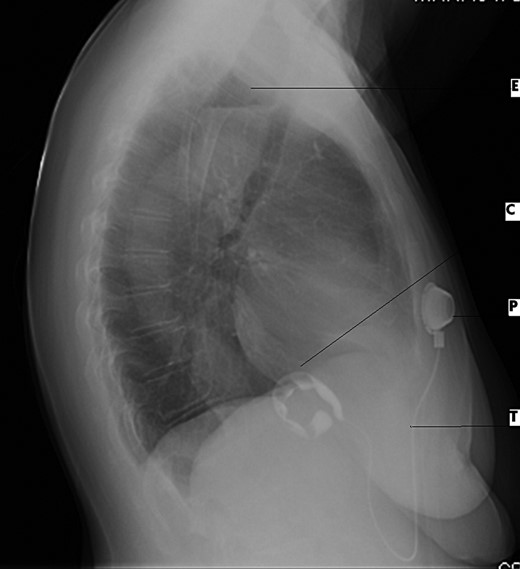

Electrocardiogram was remarkable for Q waves in leads I, aVL and V6. Chest X-ray (CXR) demonstrated a marked esophageal distention with an air fluid level (Figs 1 and 2).

Anterio-posterior CXR views demonstrate the shadow of a dilated esophagus and air fluid level (black arrow).

Lateral CXR view demonstrates dilated esophagus and fluid air level (E), contrast medium-filled inflatable inner cuff (C), connecting silicone tube (T) and subcutaneous sutured radiopaque access port (P).